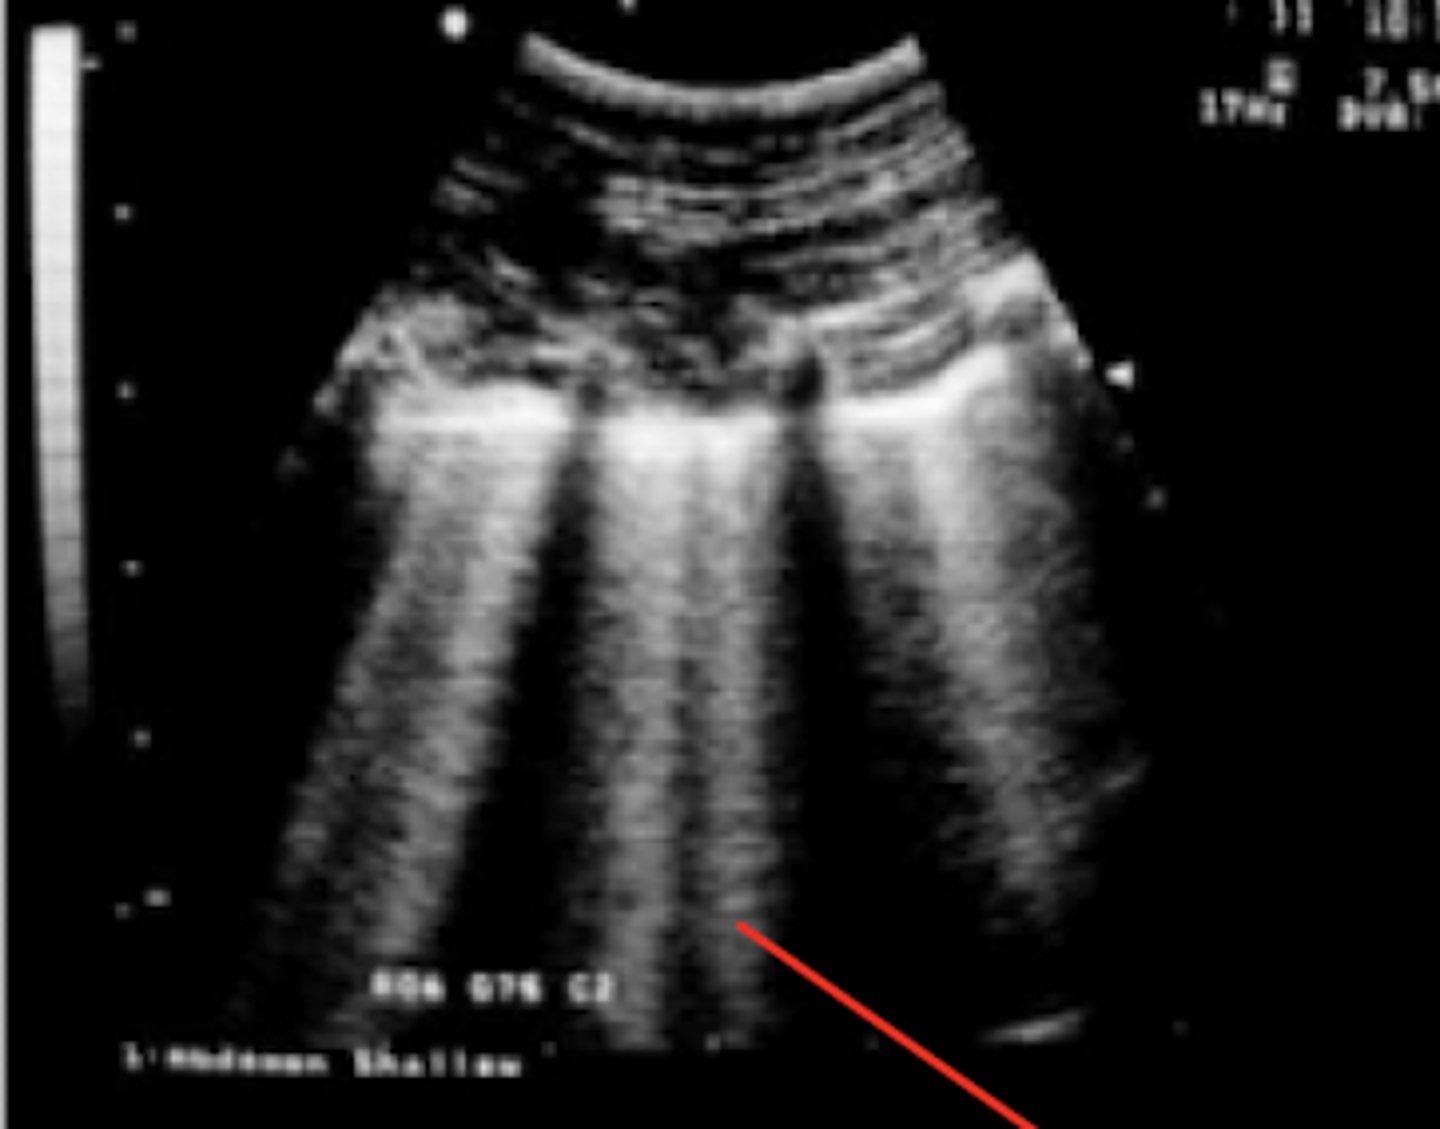

efusión abdominal

patología: